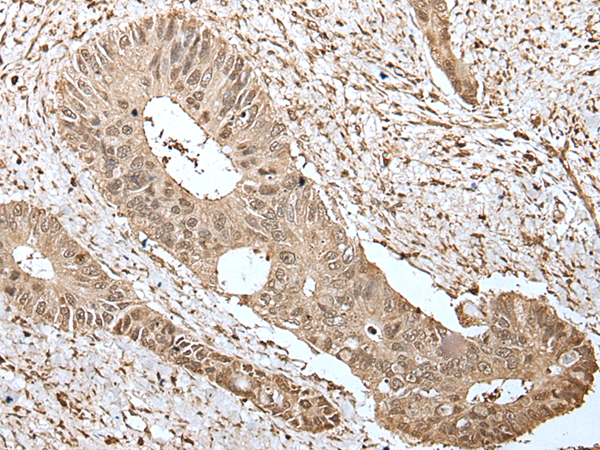

IHC positive control:

Human colorectal cancer

IHC Recommend dilution:

25-100